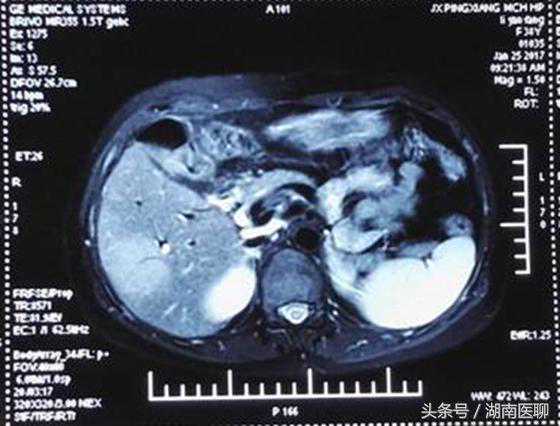

(肝脏内长了一个5公分肿瘤)

原来,李女士的肝脏内有一个直径约5公分的肿瘤,不幸中的万幸,肿瘤可能是肝细胞性肝癌,恶性程度并不是特别高。